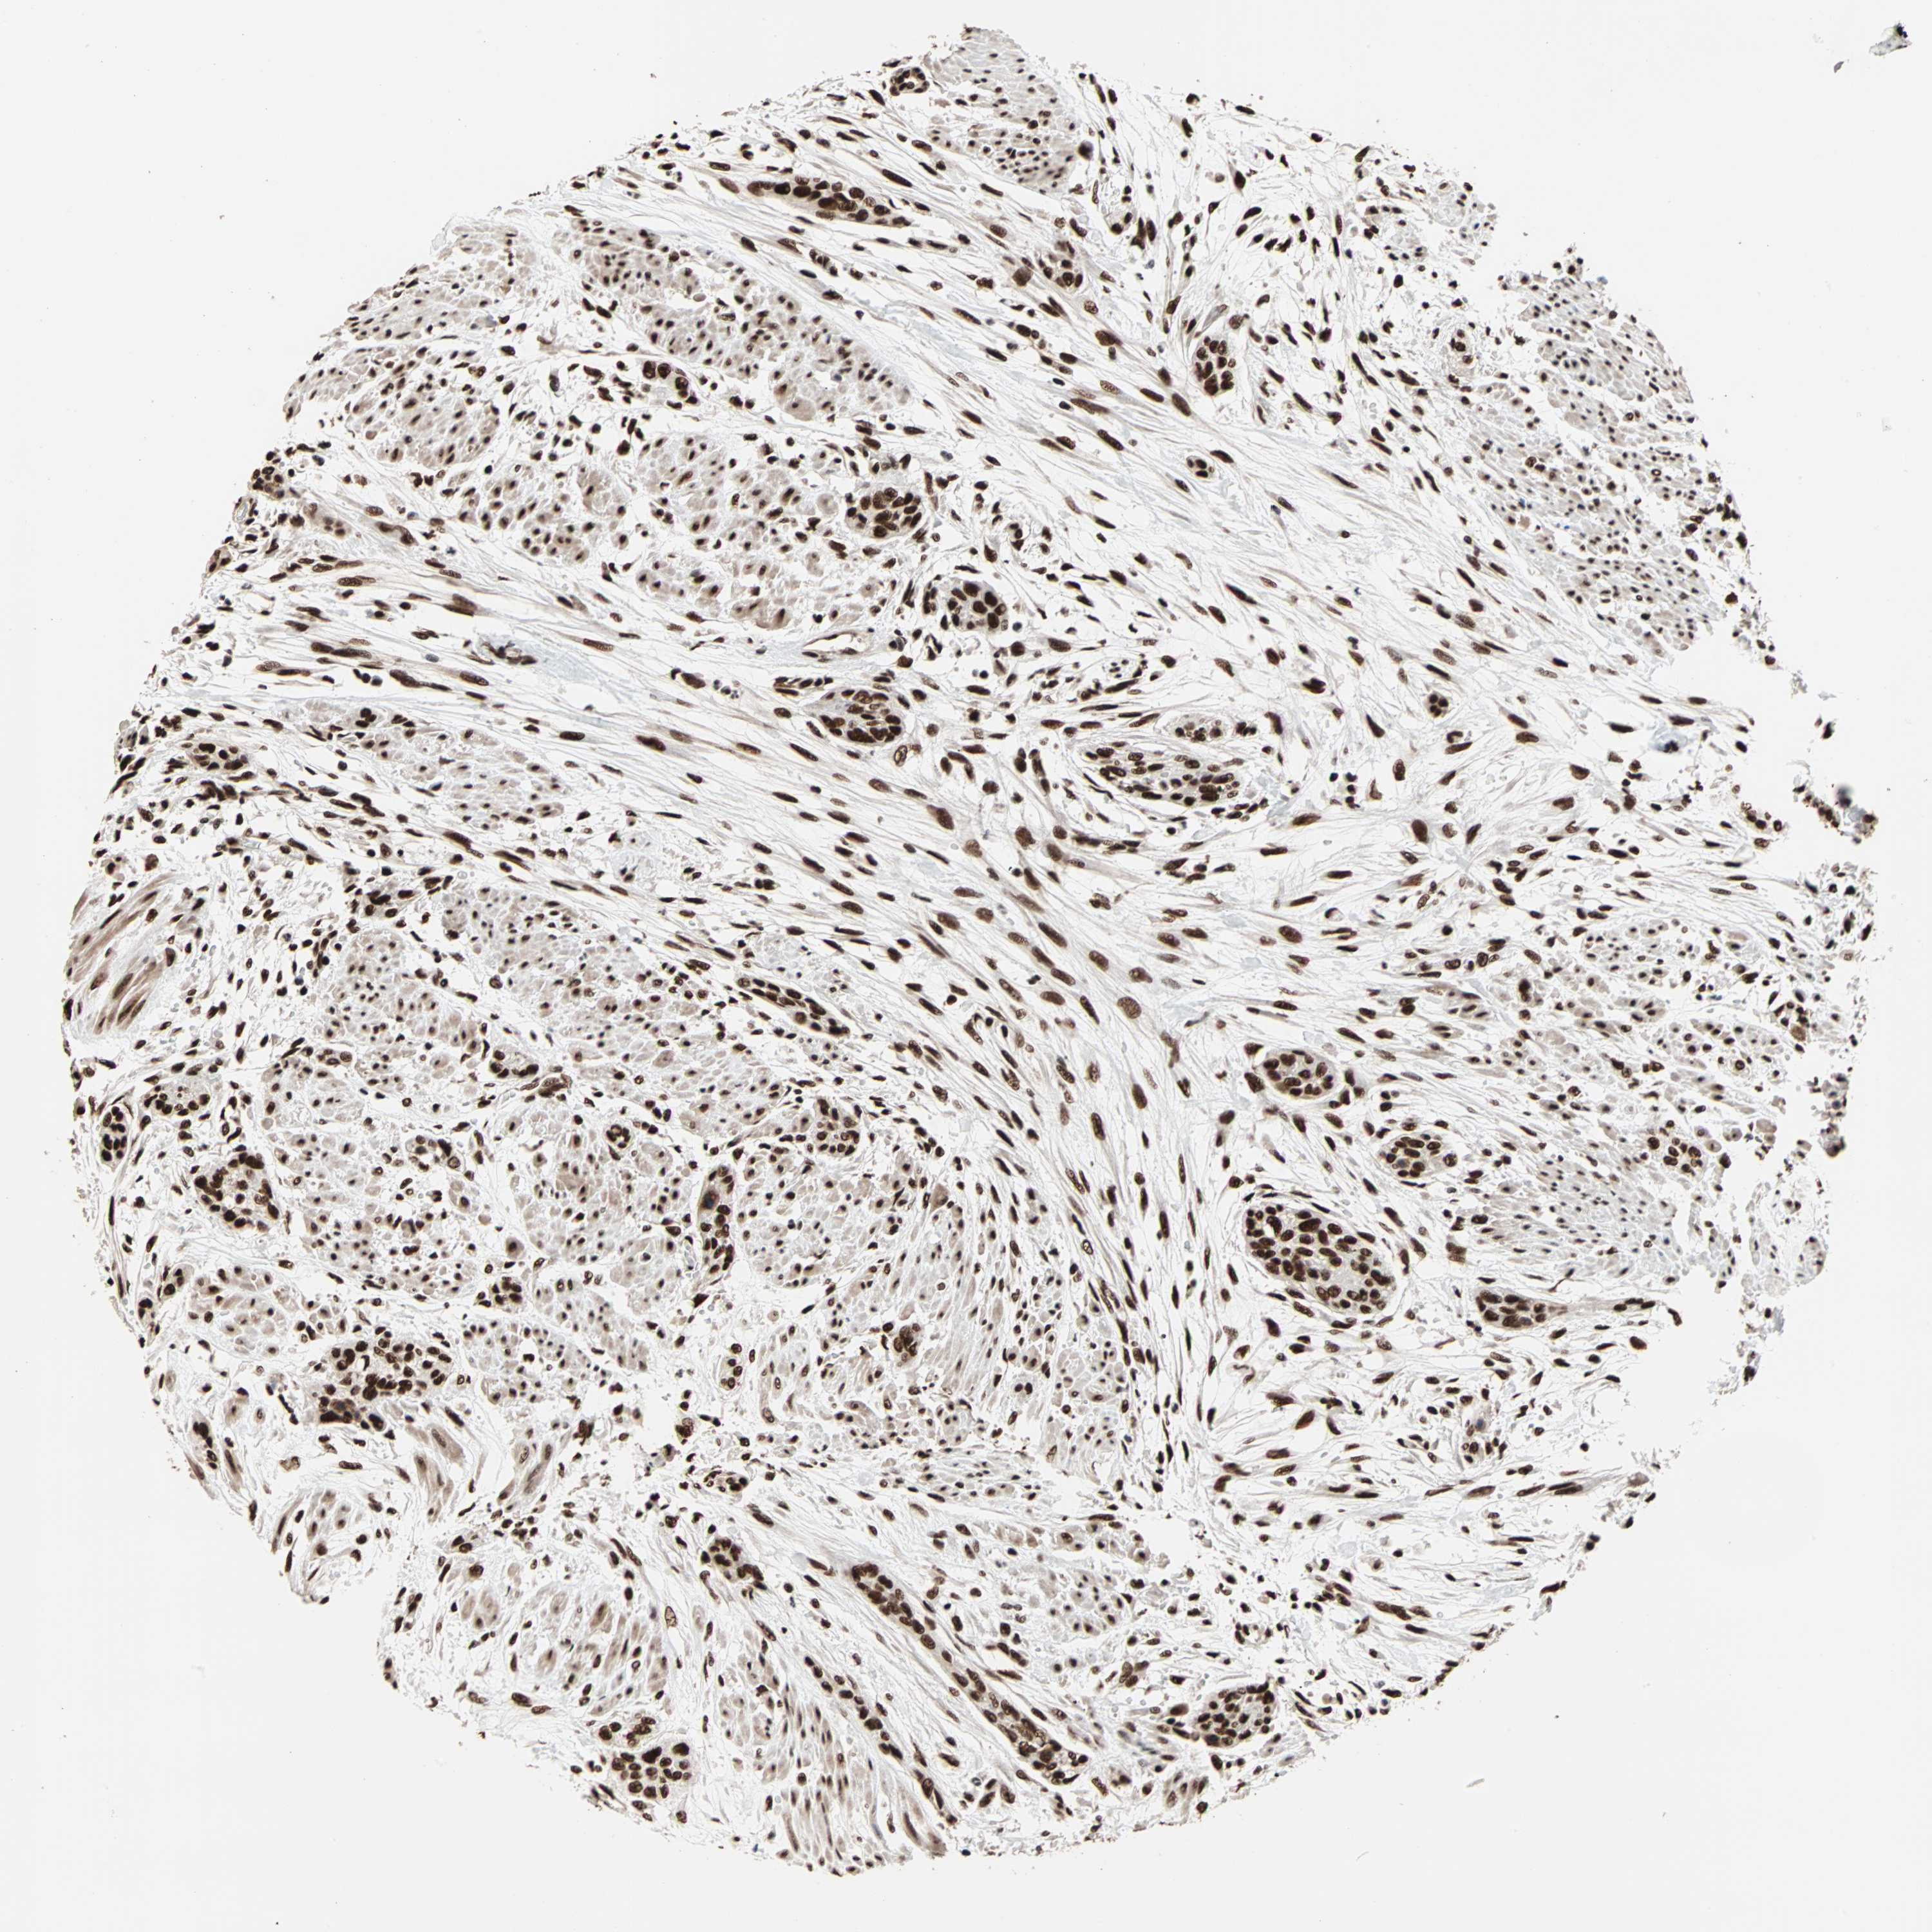

UROTHELIAL CANCER - Protein expressioni

A mouse-over function shows sample information and annotation data. Click on an image to view it in a full screen mode. Samples can be filtered based on level of antibody staining by selecting one or several of the following categories: high, medium, low and not detected. The assay and annotation is described here.

Note that samples used for immunohistochemistry by the Human Protein Atlas do not correspond to samples in the TCGA dataset.

Antibody stainingi

Antibody staining in the annotated cell types in the current human tissue is reported as not detected, low, medium, or high, based on conventional immunohistochemistry profiling in selected tissues. This score is based on the combination of the staining intensity and fraction of stained cells.

Each image is clickable and will lead to virtual microscopy that enables deeper exploration of all samples and also displays staining intensity scores, fraction scores and subcellular localization as well as patient and tissue information for each sample.

Antibody HPA007484

Staining

High

Medium

Low

Not detected

Intensity

Strong

Moderate

Weak

Negative

Quantity

>75%

75%-25%

<25%

None

Location

Nuclear

Cytoplasmic/membranous

Cytoplasmic/membranous,nuclear

Urothelial carcinoma, Low grade

Urothelial carcinoma, High grade